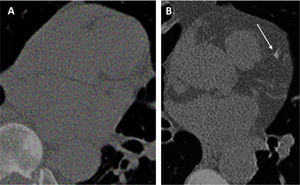

Tobacco smoking is a well-established risk factor for CVD, COPD, and LC. In LC screening cohorts, which primarily include current and former smokers, these conditions are the leading causes of death,2,3,91,92 and are often referred as the ‘Big 3 killers’. Using AI to extract comorbidity-related biomarkers from baseline LDCT images offers a valuable opportunity to enhance LC screening. AI can help optimize screening schedules – such as determining when to start, how frequently to screen, and when to stop – by refining individual risk profiles.9 Although radiologists’ visual scoring of comorbidities provides adequate predictive values25,35 (Figs. 2 and 3), AI-derived biomarkers offer greater robustness and objectivity, all without increasing the clinician's workload.93 One significant proof of this concept is a DL algorithm for the automatic quantification of coronary calcium.94 The resulting calcium scoring showed a high correlation with readings from expert radiologists and demonstrated robust test-retest accuracy.94 Beyond using AI-derived CAC as a predictor of CV events in LC screening cohorts,94–97 researchers are exploring additional approaches. For instance, a model was developed that based on the extraction of the coronary calcium and juxta-cardiac fat uses a single LDCT examination and provides a 0–1 score to estimate the probability of CVD risk.98 The model's ability to predict the risk of CVD and CV mortality equalized or surpassed that of radiologists and surpassed that of other state-of-the-art DL tools.94,98,99 Examples of its application to predict CV death in subjects with no or mild CAC are shown in Fig. 5. Other DL-derived indices include the prediction of adverse events based on the left atrial volume100 and of CV risk based on epicardial adipose tissue amount alone.101

(A and B) Assessment of risk of CV disease based on the analysis of baseline LDCT with Chao et al. deep learning algorithm.98 The algorithm attributes a moderate (score=0.351) CV risk in a 55-year-old man from NLST who did not show any coronary artery calcification at baseline LDCT (A) and who died of ischemic heart disease (ICD code I250) 2004 days after randomization. The algorithm attributes a high (score=0.700) CV risk in a 70-year-old woman from NLST with mild coronary artery calcifications (white arrow) at baseline LDCT (C) and who died of acute myocardial infarct (ICD code I219) 511 days after randomization.